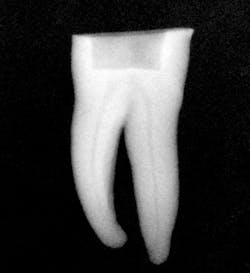

Figure 3: Radiograph showing master gutta-percha point fit to length.

I then use the Tango finishing instrument (double blue band on the latch head) in the same manner as described above. Always use the instrument wet. If you cannot achieve length, repeat the use of the Tango shaping instrument or use a 30/.04 SafeSider instrument to go to measurement. Confirm the Tango finishing instrument reaches the apical measurement. Move the instrument continuously against the canal walls until there is no resistance. I then fit the Tango-Endo gutta-percha point (figure 3). Figures 4 and 5 demonstrate the pre- and postop clinical radiograph.